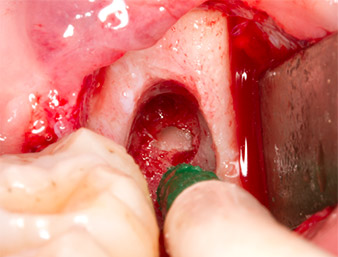

To expose the root remnant with as little trauma as possible to the tissue, a further instrument was used (Piezomed S2) that is primarily indicated for preparing the lateral window in augmentations of the sinus floor. The diamond-coated ball was additionally used to smooth sharp bone edges (Fig. 6 and 7). All the Piezomed attachments were used with the relevant automatic default setting without booster function.

Using an instrument for periodontal debridement (Piezomed P1), the periodontal ligament space of the radix relicta was then widened minimally (Fig. 8).